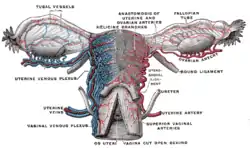

| Artery | Ovarian artery and uterine artery |

Blood supply

The uterus is supplied by arterial blood both from the uterine artery and the ovarian artery. Another anastomotic branch may also supply the uterus from anastomosis of these two arteries.

Female pelvis and its contents, seen from above and in front The arteries of the internal organs of generation of the female, seen from behind

The arteries of the internal organs of generation of the female, seen from behind Median sagittal section of female pelvis